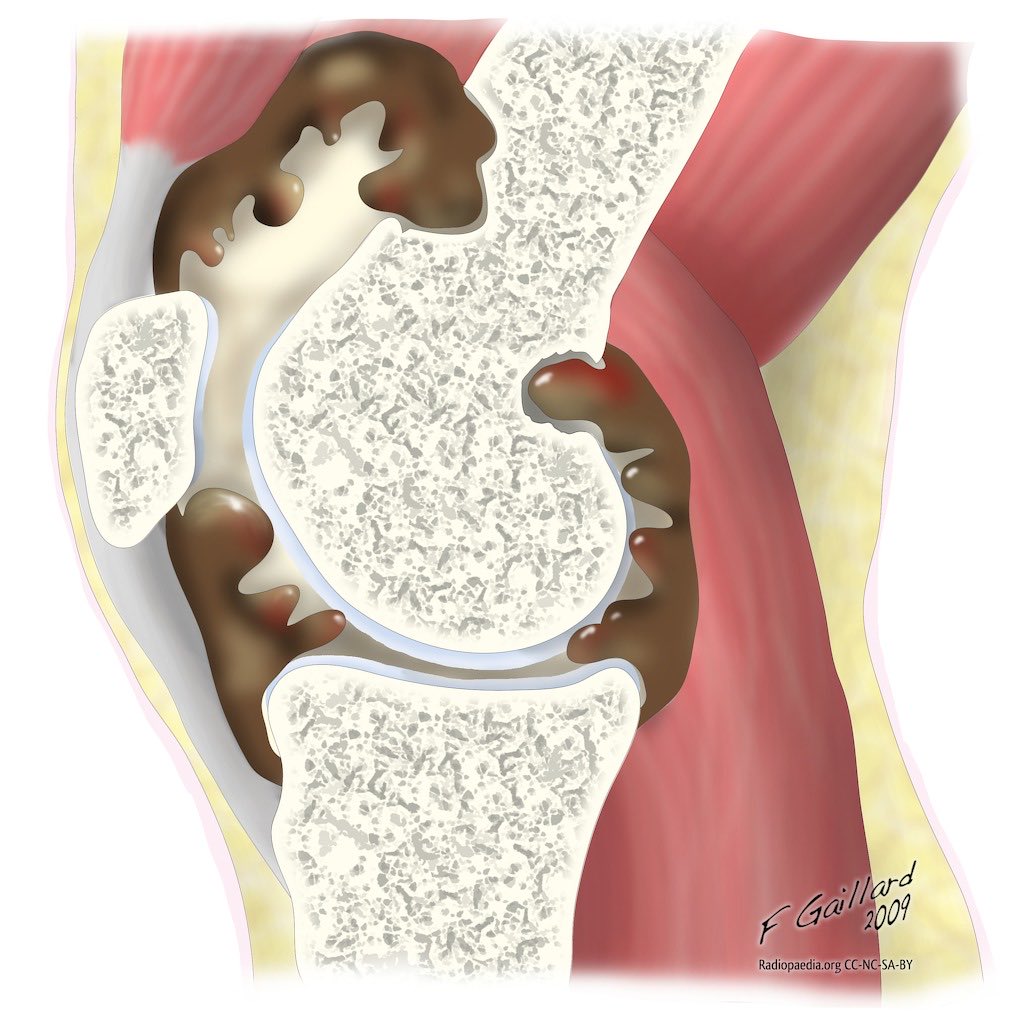

BREAKING: Utah Jazz star Jaren Jackson Jr. is likely to miss the remainder of the season to undergo surgery on his left knee to ensure his longterm health after a localized PVNS growth was discovered post trade, league sources tell me.